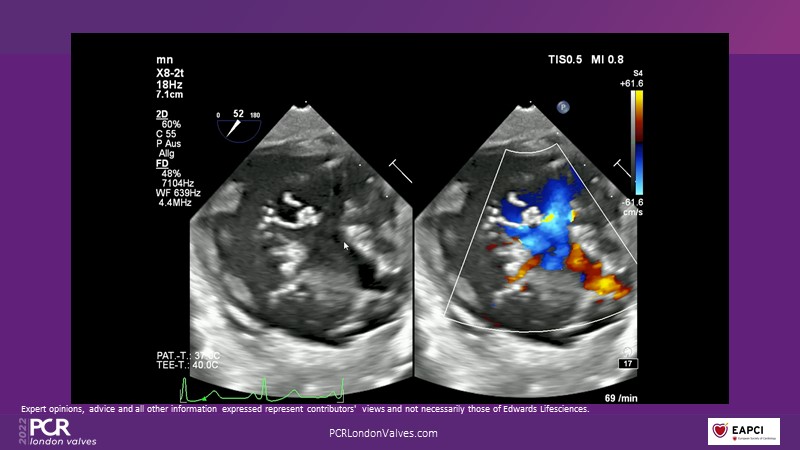

This innovative session takes you through the patient selection and anatomical characteristics when selecting amongst the different transcatheter options to treat tricuspid regurgitation, followed by a recorded demonstration using the PASCAL Precision repair system.